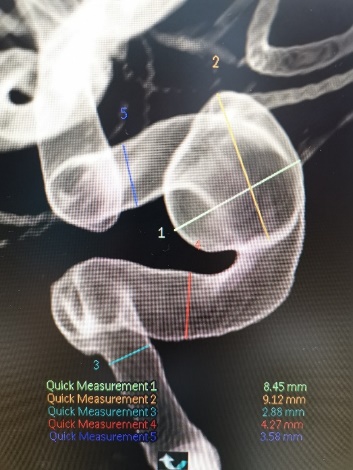

入院后行DSA检查明确右侧颈内动脉眼动脉后下方囊状动脉瘤样影,大小约1.09mm×6.53mm,宽基底,其下方见两个小囊状突起,左侧颈内动脉眼动脉后方及虹吸段均可见小囊状突起。考虑颅内多发动脉瘤。

入院后行全脑血管造影证实右侧颈内动脉眼段动脉瘤。瘤颈宽约4.91mm,瘤体最大径约8.21mm,载瘤动脉远近端血管直径分别为3.07mm、3.52mm。